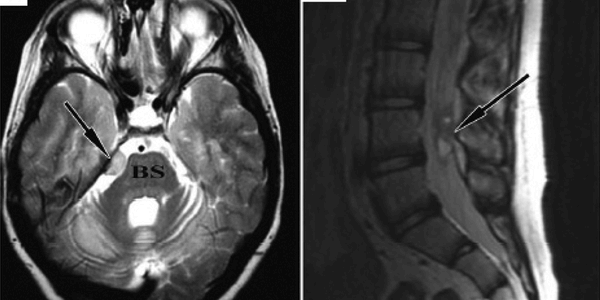

Case Study - Brain And Spinal Tumor Following Stem Cell Therapy

A case report published in PLoS Medicine describes a rare side effect of human fetal stem cell therapy. Ninette Amariglio and Gideon Rechavi from the Sheba Medical Center, Tel Aviv, Israel, and colleagues report the case of a boy with a rare genetic disease, Ataxia Telangiectasia, who underwent human fetal stem cell therapy at an unrelated clinic in Moscow and who, four years after the therapy began, was shown to have abnormal growths in his brain and spinal cord. There have been reports in rodents of the development of tumors following the injection of pluripotential embryonic stem cells…